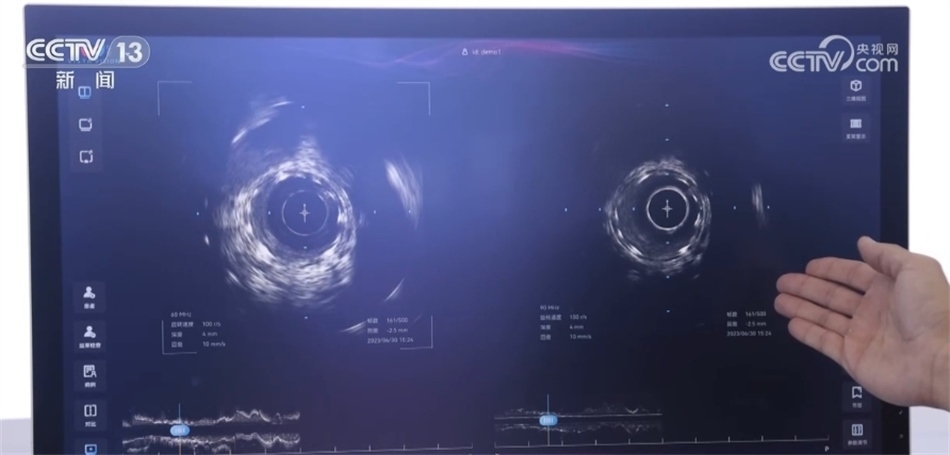

總臺央視記者 褚爾嘉:這里是一個傳統(tǒng)的血管的超聲圖像,我們可以看到血管的全貌。右邊這里是一個工作頻率高達100兆赫茲的超高頻的血管內超聲圖像,通過技術升級,現(xiàn)在我們可以更加清晰地看到冠狀動脈的精細結構,這也是目前世界上清晰度最高的一個血管內的超聲圖像。

中國科學院深圳先進技術研究院研究員 馬騰:在醫(yī)學影像領域,圖像的分辨率和深度是不可兼得的。我們創(chuàng)新性地將一個超高頻的探頭和一個傳統(tǒng)的探頭融入到一個導管里,在不改變導管尺寸的情況下,可以為醫(yī)生提供一個大深度、高精度二者兼得的圖像。對于一些冠狀動脈急性病癥,包括斑塊的診斷以及介入手術的治療,會給醫(yī)生提供一個更加全面、更加有效的醫(yī)療影像學工具。